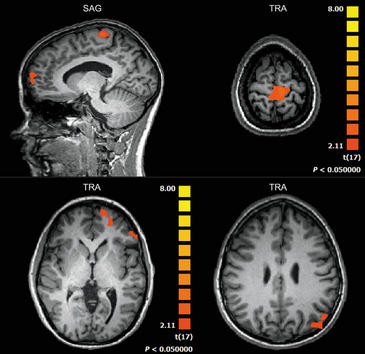

Un equipo europeo, con participación de la Universidad Pompeu Fabra (España), ha detectado que las áreas cerebrales asociadas al control motor se activan cuando se ‘juega’ con el sistema de rehabilitación virtual RGS de pacientes con lesiones cerebrovasculares. Una técnica de resonancia magnética permite visualizar las imágenes.

Mediante una técnica de resonancia magnética –functional Magnetic Resonance Imaging o fMRI– se ha medido el flujo sanguíneo en las zonas activas del cerebro y se ha analizado la activación de las neuronas espejo en las áreas corticales, frontales y parietales de este órgano.